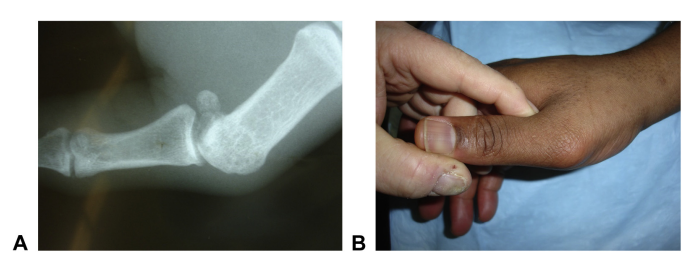

손가락 관절은

어떤 각도에서도 옆으로 꺾이지 않도록

매우 견고하게 설계되어 있는데요.

단단하게 잡아주는 역할을 하는 것이

바로 양옆에 붙어있는'측부인대(Collateral Ligament)'입니다.

손가락 측부인대가 손상되면서

멍, 통증, 부종이 생기는 거죠.

3단계는 손가락 인대가 완전 파열된 상태로**

관절이 옆으로 꺾일 때 아무 저항 없이 덜렁거리고

극심한 불안정성을 보입니다.